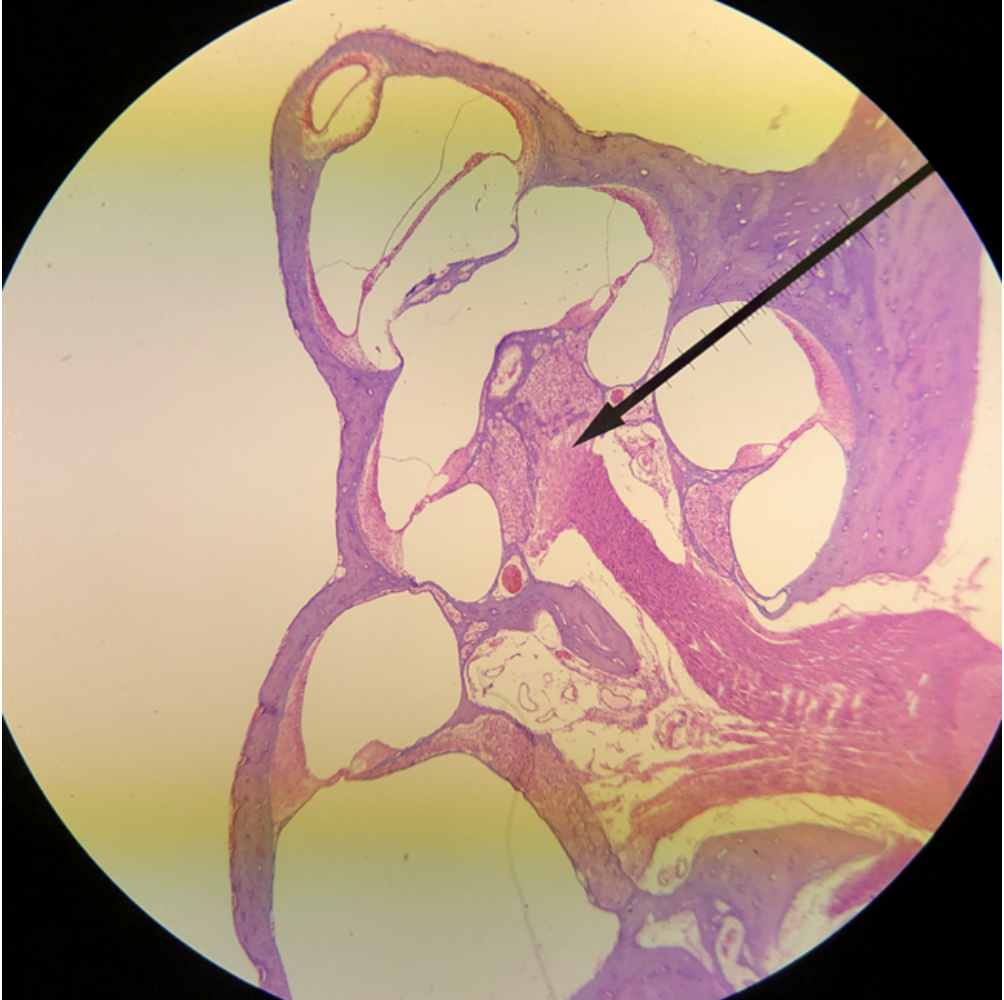

In the image above, identify the main structure seen in the field of view.

cochlea